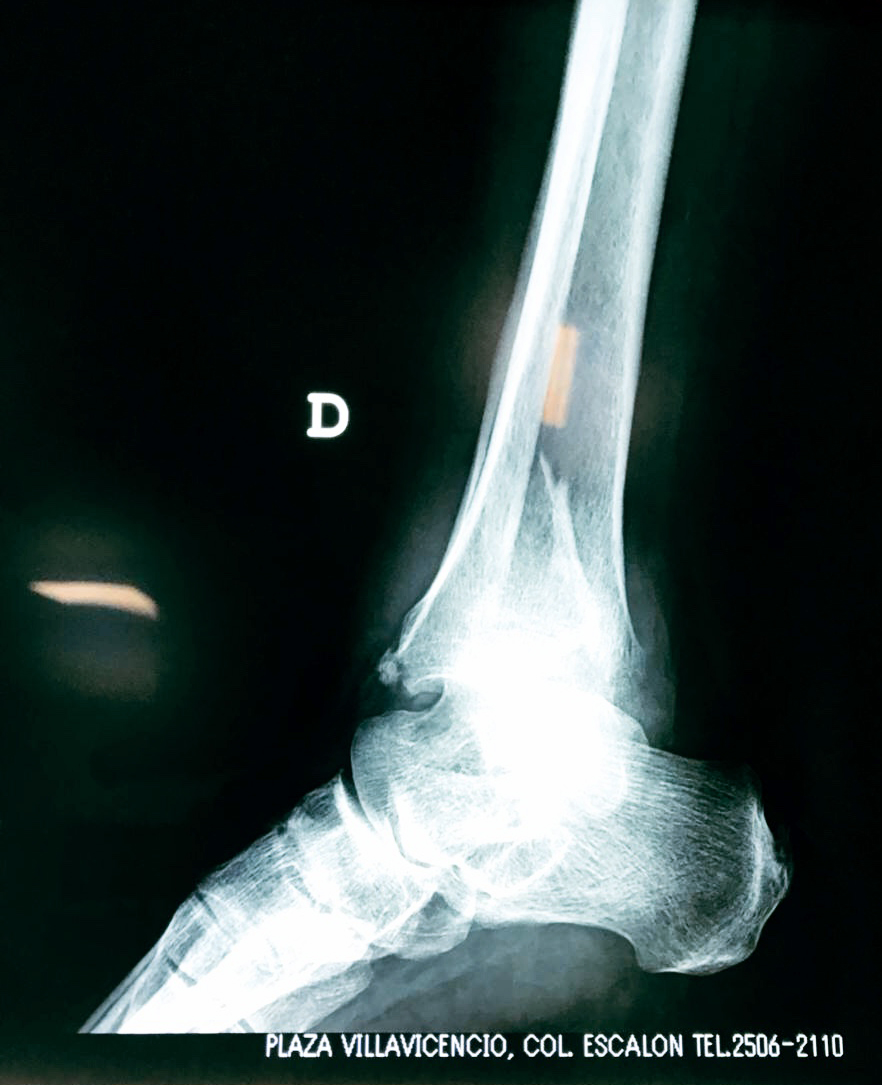

Una fractura de tobillo es la rotura de uno o más de los huesos del tobillo. Estas fracturas pueden ser:

Algunas fracturas de tobillo pueden requerir cirugía si:

- Los extremos de los huesos están desalineados entre sí (desplazados).

- La fractura se extiende hasta la articulación del tobillo (fractura intra-articular).

Cuando se necesita cirugía, es probable que esta implique el uso de clavijas de metal, tornillos o placas para sostener los huesos en su lugar mientras la fractura se consolida. Los elementos de soporte pueden ser temporales o permanentes.